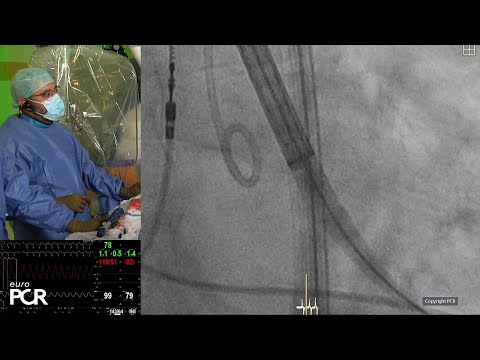

Securing coronary access during and after TAVI - PCR Valves e-Course 2020